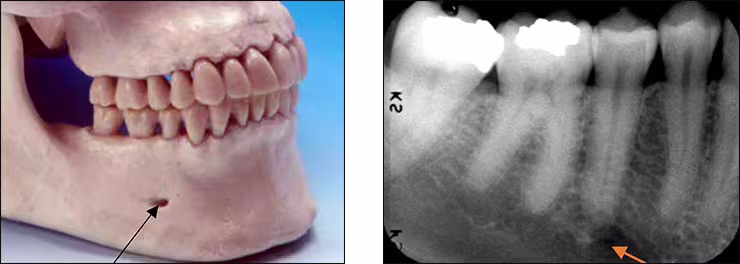

Mental foramen – The mental foramen, the primary landmark of this area, is a circular radiolucent structure located below the roots of the mandibular premolar teeth. This structure is the opening for passage of the mental nerve and vessels and can be observed on mandibular premolar and the lateral aspect of canine periapical images. This bilateral radiolucency can be misinterpreted as a periapical lesion. However, it is easily differentiated upon closer examination of the tooth and its supporting structures.